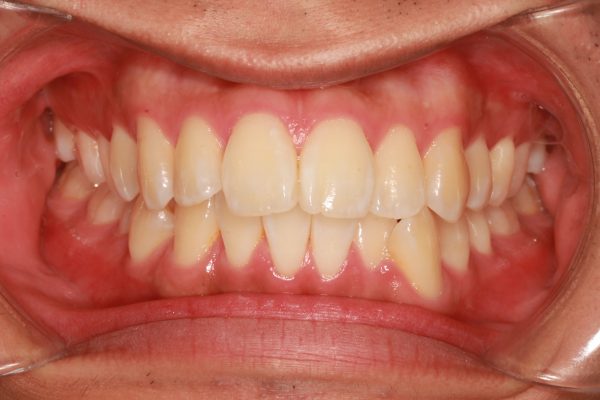

口ゴボ治療後

治療期間は2年1か月でした。

抜歯を行ったことで、前歯が下がり、上顎の前後的な距離が適正になりました。

上下の顎が適正な長さになった、この効果で上下の前歯が下がりました。

口ゴホ治療前後

治療前後で前歯の傾斜がかなり改善しました。

口もと の出っ張り感が 解消され、自然に お口が閉じられるように なりました。

前歯が大きく下がったことで、 ”出っ歯” 感も解消し、